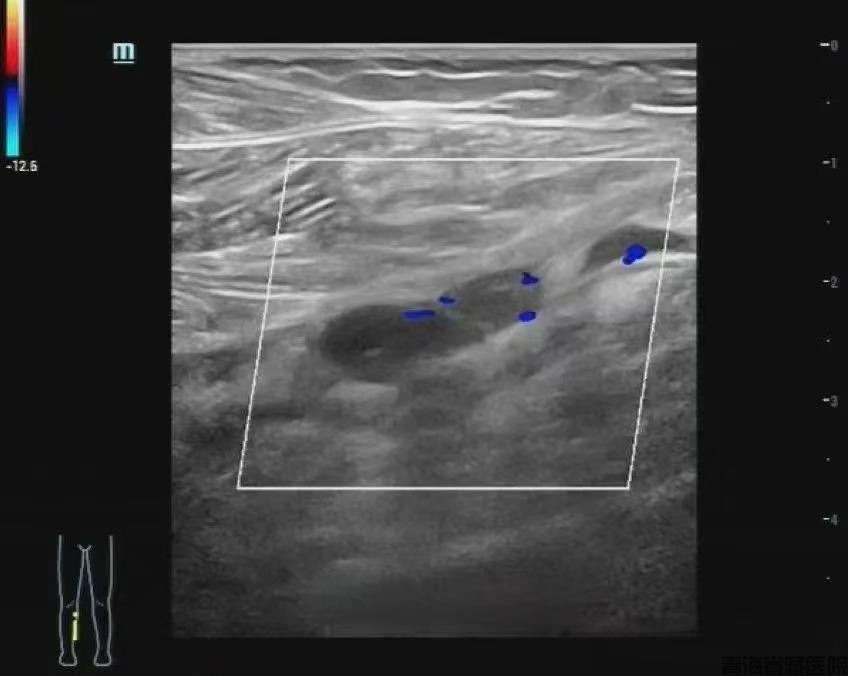

图片3.png

图片4.png

彩色多普勒超声检查

管腔内未见彩色血流信号,进一步提示静脉管腔内血栓形成